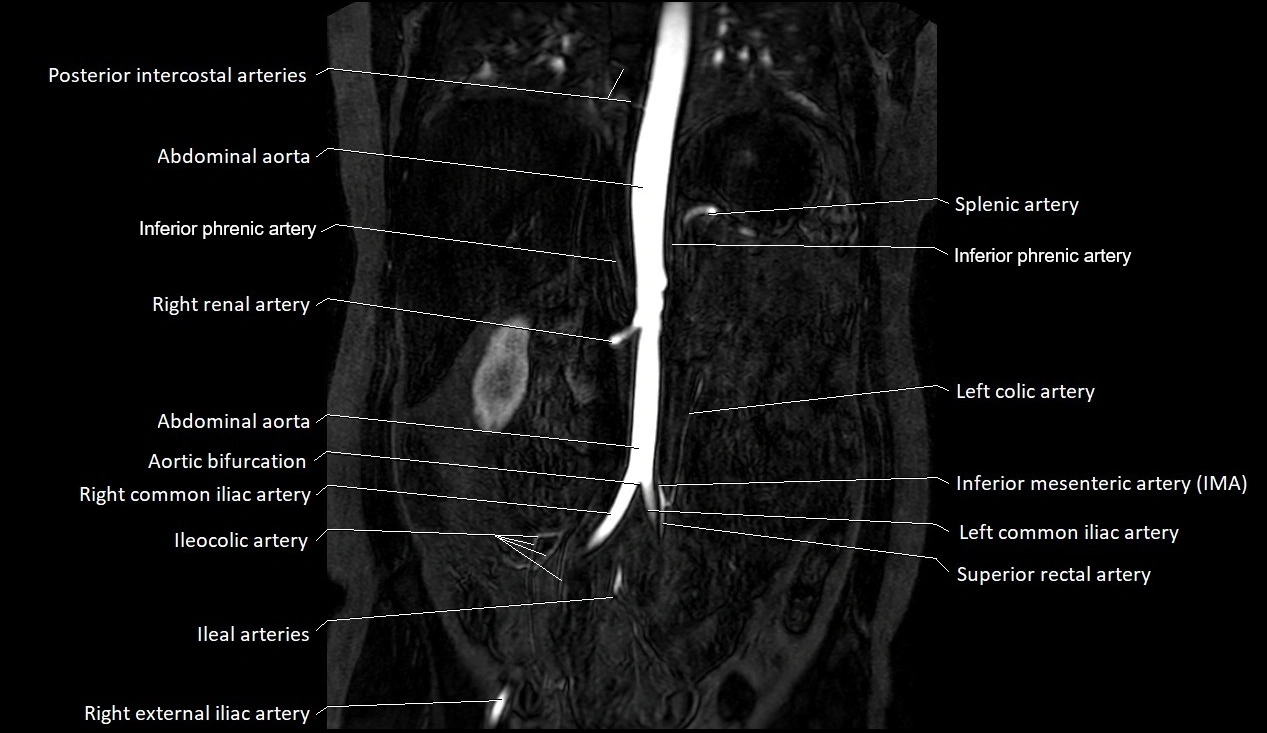

MRI images

image